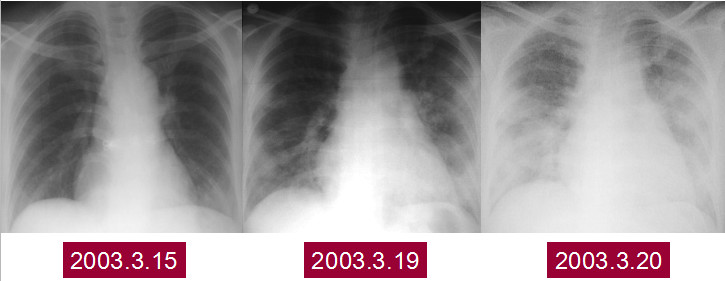

这是一个患有SARS的病人,在2003年非典时期。刚开始只有左下肺有实变影,4天后,两肺的实变影对称,但是发展迅速,又过了1天,表现为两侧肺对称性的实变影,呈类似肺水肿改变。

SARS